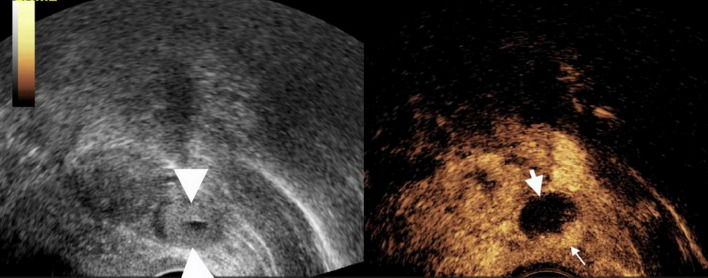

Results: A total of 21 patients were included: 19 with tEP, 1 with ovarian pregnancy, and 1 with intrauterine pregnancy. The sensitivity, specificity, and accuracy of transvaginal ultrasound (TVUS) for diagnosing tubal dilation were 15.8%, 100%, and 23.8%, respectively. For CEUS, these values were 94.7%, 100%, and 95.2%, respectively. Statistically significant differences were observed between CEUS and TVUS in sensitivity and accuracy (P = 0.000). The enhancement pattern of villous tissue was categorized as either circular or non-circular. Among the tEP cases, 2 exhibited circular enhancement and 17 showed non-circular enhancement. Based on positive β-HCG, absence of an intrauterine gestational sac, and sonographic visualization of a dilated fallopian tube containing either circular or non-circular enhancement internally, CEUS demonstrated high diagnostic accuracy for tEP diagnosis in cases with low β-HCG levels. CEUS correctly diagnosed 18 of 19 tEP cases. One tEP case was diagnosed as a mass of uncertain significance. The intrauterine pregnancy case was misdiagnosed as an EP. The ovarian pregnancy case was diagnosed as EP, though CEUS indicated a relatively high possibility of ovarian origin.

Conclusion: In conclusion, CEUS holds significant diagnostic value for tEP. It is particularly useful in diagnostically unclear cases and provides a more detailed assessment of the internal structure of adnexal masses.